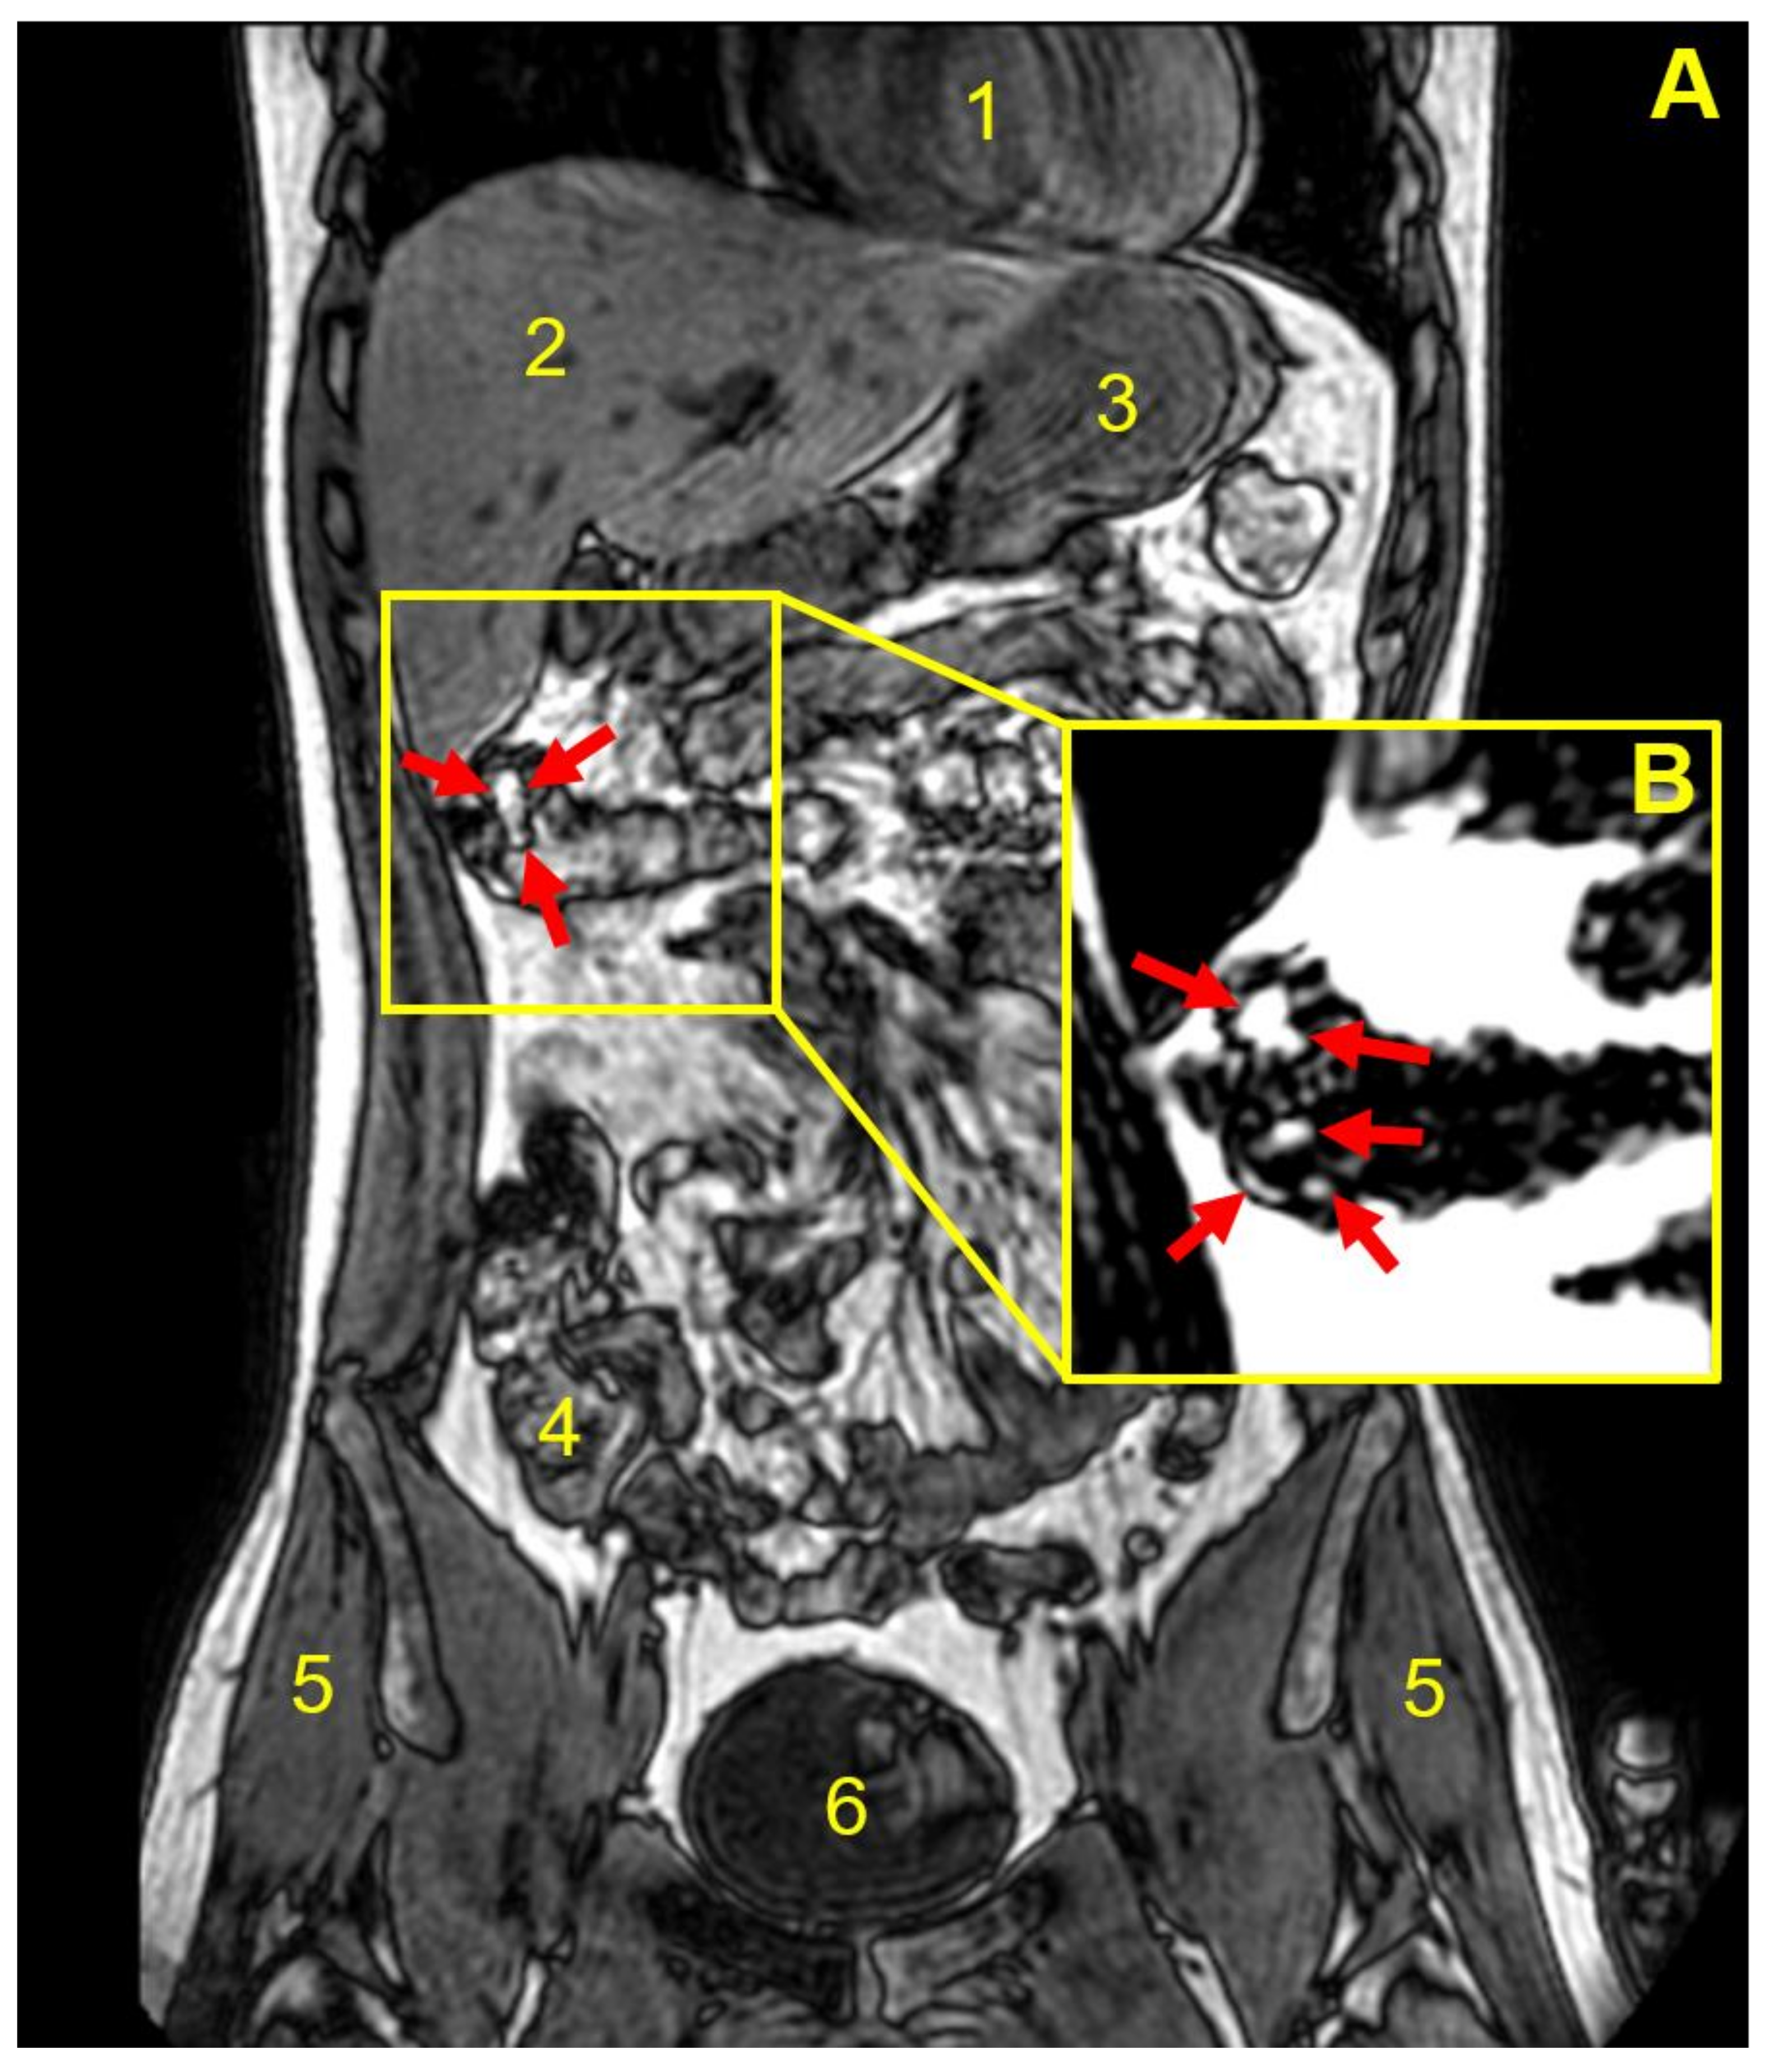

3.3. Capsule Imaging Studies In Vivo

| Participant | Weight Gain (mg) a | Weight Gain Per Surface Area (mg/mm2) | Gastrointestinal Location and Integrity of the Capsule at the Different Imaging Time Points (min) | |||||||

|---|---|---|---|---|---|---|---|---|---|---|

| 45 | 90 | 135 | 180 | 225 | 270 | 315 | 360 | |||

| 1 | 9.2 ± 0.8 | 0.02 | Stomach | Stomach | Stomach b | NO c | NO | NO | NO | NO |

| 2 | 18.2 ± 1.2 | 0.04 | Stomach | Stomach | Duodenum | Duodenum | Term ileum | NO | NO | d |

| 3 | 18.2 ± 1.2 | 0.04 | Stomach | Stomach | Term ileum | Asc colon | Hep flexure | Hep flexure | Hep flexure | Hep flexure |

| 4 | 18.2 ± 1.2 | 0.04 | Stomach | Jejunum | Jejunum | Jejunum | Term ileum | Term ileum | Term ileum | NO |

| 5 | 18.2 ± 1.2 | 0.04 | Stomach | Jejunum | Cecum | Cecum | Asc colon | Asc colon | NO | Hep flexure |

| 6 | 18.2 ± 1.2 | 0.04 | Stomach | Stomach | Term ileum | Term ileum | NO | NO | NO | NO |

| 7 | 18.2 ± 1.2 | 0.04 | Stomach | Jejunum | Jejunum | Term ileum | Term ileum | NO | NO | NO |

| 8 | 36.0 ± 5.2 | 0.08 | Stomach | Jejunum | Term ileum | Cecum | NO | NO | shade | |

| 9 | 52.6 ± 9.7 | 0.11 | Stomach | Duodenum | Term ileum | Hep flexure | Hep flexure | Trans colon | Trans colon | |

| 10 | 52.6 ± 9.7 | 0.11 | Stomach | Stomach | Duodenum | Duodenum | NO | NO | ||